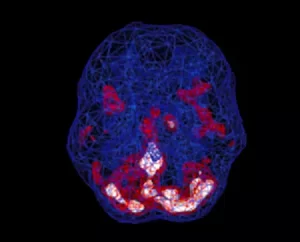

Estudos de imagens cerebrais mostram que a depressão não é uma falha de carácter ou fraqueza pessoal. Está

associado a mudanças biológicas no cérebro. Pessoas com depressão geralmente têm muita atividade no sistema límbico profundo – os centros emocionais do cérebro. Mas nem todos com depressão têm os mesmos padrões cerebrais subjacentes. Nas nossas investigações, a imagem cerebral mostrou-nos que existem 7 padrões cerebrais diferentes associados à depressão, e conhecer o seu tipo pode ser a chave para obter o tratamento mais eficaz

SPECT (tomografia computadorizada por emissão de fóton único) é um estudo de medicina nuclear que avalia o fluxo sanguíneo e a atividade no cérebro.

Basicamente, ele mostra três coisas: atividade saudável, pouca atividade ou muita atividade. Uma varredura “ativa” saudável mostra as partes mais ativas do cérebro com azul representando a atividade média e vermelho (ou às vezes vermelho e branco) representando as partes mais ativas do cérebro. No exame saudável à esquerda, a área mais ativa está no cerebelo, na parte posterior/inferior do cérebro. A imagem do cérebro à direita mostra hiperatividade no sistema límbico profundo (o centro emocional do cérebro), um padrão comumente visto na depressão.https://www.youtube.com/watch?v=KZtYA–Yvjs